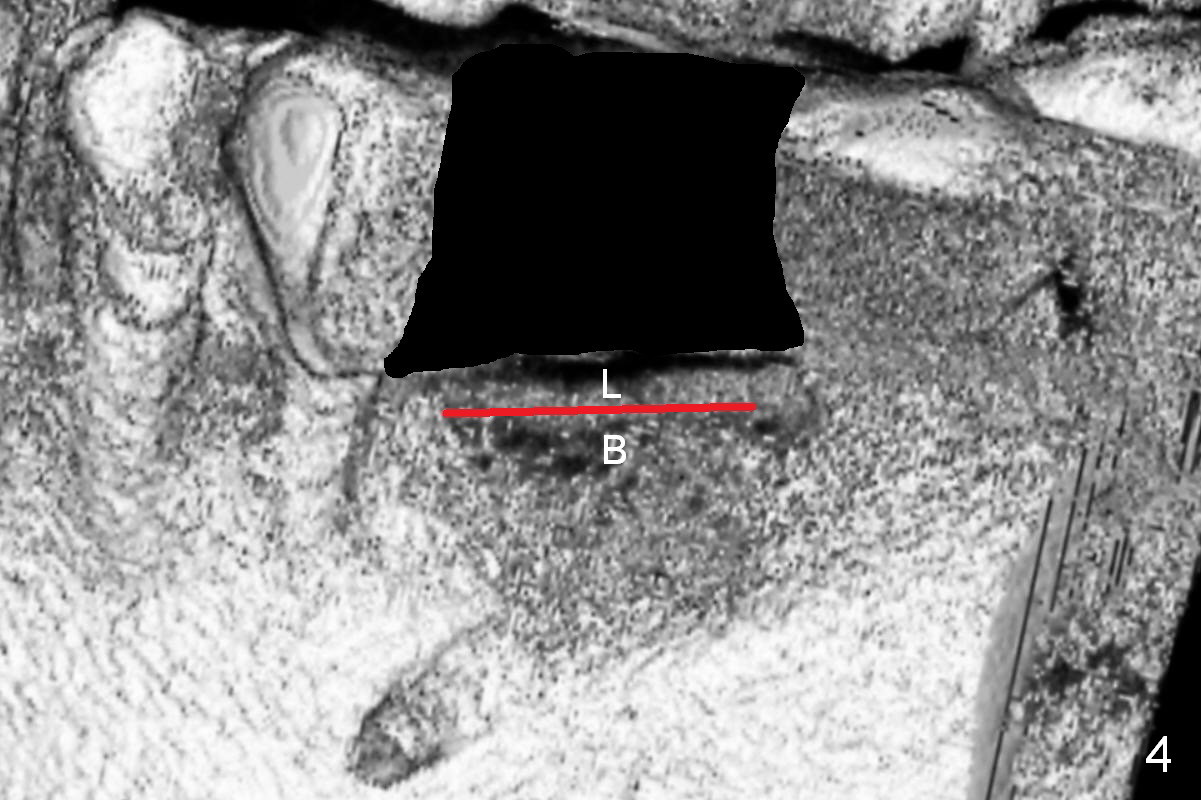

Bone density at the crest appears to be low (Fig.3 arrowheads).  After pontic removal (Fig.4 black area) and incision, use #15 scalpel, bone scalpels and bone blades to start bone expansion (red line).  Bone expansion continues with D osteotomes (Fig.5 red area) which mainly moves the buccal plate (B) buccally.  The 3rd step of bone expansion is to use RT (round tapered) osteotomes or bone expanders (Fig.6 white circle); the buccal plate keeps being expanded more the lingual one (L).  When an implant is placed, the lateral spaces created by expansion will be filled with bone graft.  If the depth of osteotomy is not enough, use drills to reach the desired one.